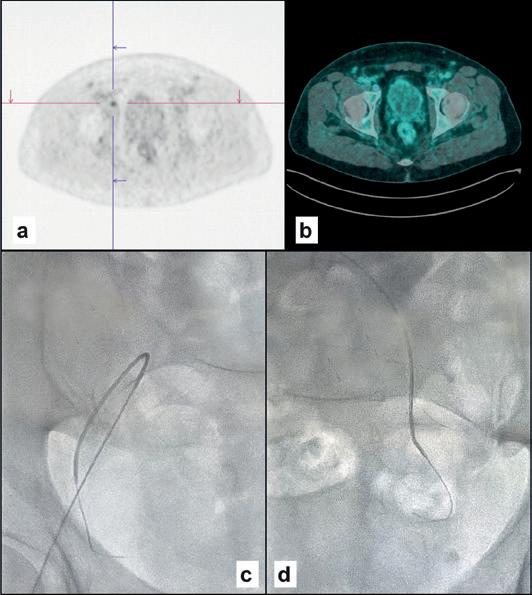

ASE THREE

Female, 83 years old

Uveal melanoma, left eye (A). Right transfemoral catheterisation of the left jugular vein (B, C) with finding of HNF1A mutation indicating a poor prognosis.

FOUR

Male, 63 years old

Operated prostate adenocarcinoma, Gleason grade 7 (3+4), PSA increase to 0.26 six years after surgery. PET PSMA (A, B) positive for right pelvic adenopathy. In the right hypogastric vein (C) we found ESR1, FGFR2 and MAP2K1 mutations. In the left (D) vein, mutations were FGFR2, MAP2K1 and RET. Pelvic radiotherapy is indicated.